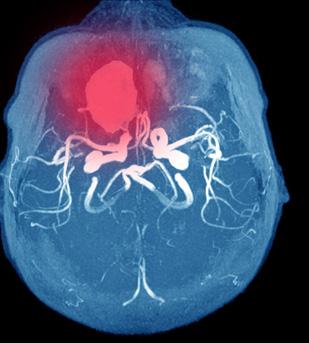

Bakgrunn for PERT Lungeemboli (LE) er en betydelig bidragsyter til morbiditet og mortalitet. Det er den tredje vanligste årsaken til kardiovaskulær død på verdensbasis etter hjerteinfarkt og hjerneslag (1, 2). Samtidig ser man også at insidensen fortsetter å øke (2). Symptomer og klinikk ved lungeemboli er utfordrende ettersom de kan variere fra en asymptomatisk tilstand til en hemodynamisk ustabil situasjon, og i verste fall død. Diagnostikk og behandling av lungeemboli skiller seg fra andre medisinske tilstander ved at den kan involvere både indremedisinske, kirurgiske og radiologiske spesialiteter. Det finnes heller ingen standardisert eller systematisk tilnærming for behandlings- og beslutningsstøtte når pasienter med lungeemboli presenterer med et mer sammensatt bilde (1). Evidensgrunnlaget for behandling av denne pasientgruppen baserer seg i stor grad på ikke randomiserte studier, registerdata og ekspertuttalelser. Samtidig foreligger det også en betydelig heterogenitet i behandlings anbefalinger hos lungeembolipasienter (2). Mangelen på ovenstående samt økt tilgjengelighet av behandlingsmuligheter, herunder systemisk trombolyse, kateterbasert behandling, kirurgisk trombektomi og sirkulasjonsstøttende behandling

som ECMO førte til at det i 2012 ble innført «Pulmonary Embolism Respons Team» (PERT) ved Massachusetts General Hospital (1, 3).

PERT-prinsippet

Prinsippet for PERT bygger på samme konsept som andre multidisiplinære akuttmedisinske team, herunder særlig de amerikanske Heart Team, Stroke Team og Rapid Response Team. Som disse har PERTmodellen til hensikt å ivareta akutte komplekse lungeembolipasienter strømlinjeformet der man gjennom en multidisiplinær tilnærming får en rask og korrekt risikostratifisering, bestemmer den beste terapeutisk tilnærming for hver pasient og mobiliserer nødvendige ressurser for å oppnå dette. Etableringen av PERT er per dags dato en klasse IIa anbefaling i European Society of Cardiology guidelines fra 2019 (4) og håpet er å kunne reduserer mortalitet og morbiditet hos pasienter med en potensielt livstruende og ofte komplisert tilstand (1, 5).